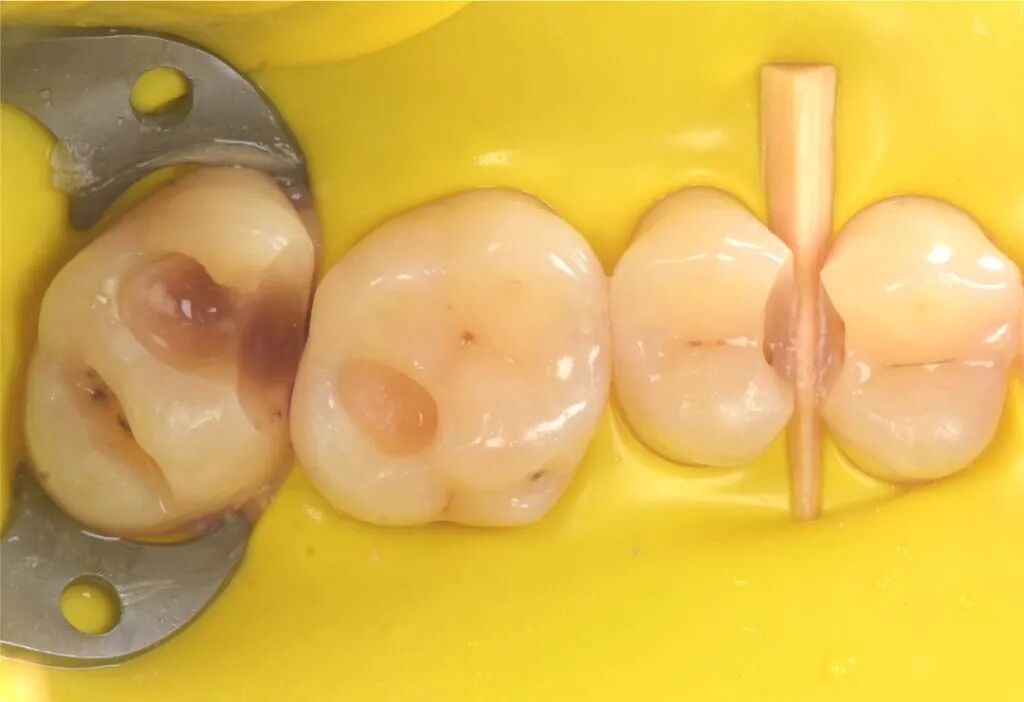

图1. 一位患者主诉左上后牙食物嵌塞咬合不适。左上象限(从第一前磨牙至第二磨牙)龋病情况如图。

图2. 在与患者讨论完治疗方法和风险后,清除龋损,恢复牙齿形态和功能是主要目标。

图3. 局部麻醉,橡皮障隔离,清理牙齿。